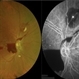

- FFA picture of LE of a 48 year male patient with a choroidal melanoma.